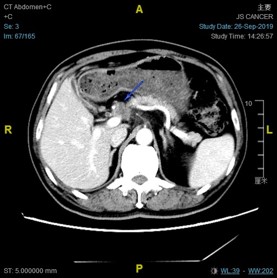

2016-03-03复查CT:左下肺结节增大,考虑转移;肝脏新见结节,不除外转移;上腹术后改变较前相似;右甲状腺病变基本同前。

2016-3-3:

RECIST1.1: 肝脏病灶8.7毫米增大到12.1毫米,左下肺病灶14.5毫米缩小到8毫米。疗效评价:稳定。